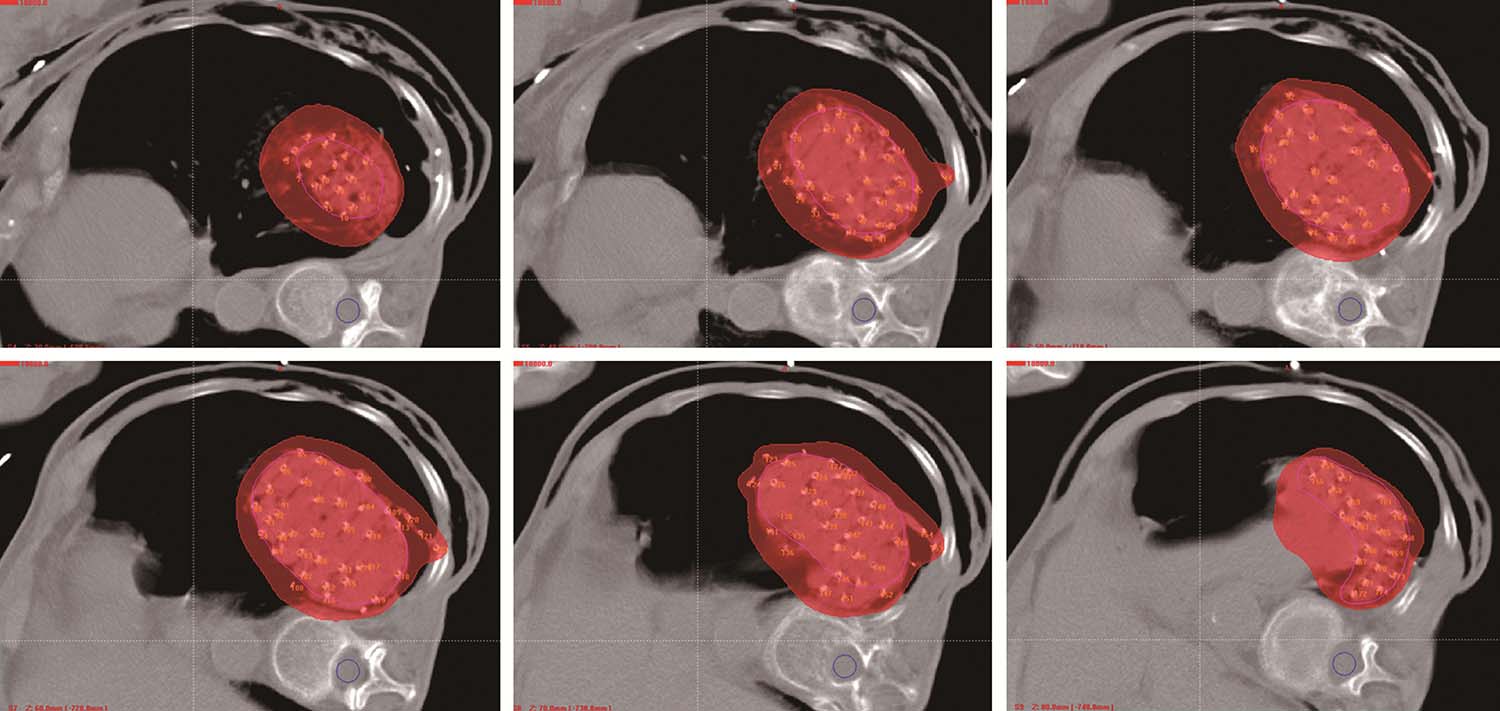

所有患者术前3天行强化CT扫描,依据病灶部位采取仰卧、俯卧、侧卧等体位,真空负压垫固定。拷贝DICOM格式CT图像传输至近距离TPS设计术前计划,临床医生与物理师共同勾画肿瘤靶区体积(GTV)和邻近危及器官(OAR),设定处方剂量和粒子活度,根据病灶位置及与周围重要脏器的关系,设计进针路线,模拟粒子空间分布,确定粒子间距及排布方式,计算粒子数目,计算GTV及OAR的照射剂量,得出剂量体积直方图(DVH)及逐层等剂量分布图。

患者取与术前CT扫描相同体位,真空负压垫固定体位,防止穿刺过程中因体位变动给穿刺带来的不利影响。将导航支架与CT碳纤维床板相连接,以0.5cm层厚扫描,选取病灶中心层面,将一个预定进针点在皮肤表面做出大十字标记,消毒、铺巾、局麻,安装模板,用激光灯校准模板,使激光灯的 x 轴和 y 轴投影与模板表面的标记线相重合,利用数字化角度仪或者水平仪调整模板的角度和方向,使模板在 y 轴方向的角度为零,调整 x 轴方向的角度,与术前计划保持一致。选择病灶中心层面,参考术前计划,将数根穿刺针抵达皮肤表面,扫描观察针尾走行方向,再次校准模板,然后测量进针的深度,完成该层面的进针,如果是肺等移动度较大的脏器,可以先插入2~3根固定针,将病灶与模板迅速“绑定”(图4-3-1),然后再依次完成其他层面的进针,如果遇到坚韧骨骼遮挡,使用捻针或骨钻打孔技术破骨插植,待完成所有层面的进针以后再植入粒子。

图4-3-1 进针过程

例1 患者男性,72岁,左肺鳞癌侵犯胸壁并同侧肺门淋巴结转移,T4N1M0。2018年1月16日行共面模板引导放射性粒子植入术(图4-3-2~图4-3-7)。

图4-3-2 术前布针三维重建图

图4-3-3 模板引导,完成选择层面的进针

图4-3-4 依次完成其他层面的进针

图4-3-5 完成肺门病灶的进针

图4-3-6 完成肺门病灶的粒子植入

图4-3-7 术后等剂量分布图

例2 女性,76岁,左肺周围型腺癌,T4N0M0,2017年10月12日行共面模板引导放射性粒子植入术(图4-3-8~图4-3-13)。

图4-3-8 术前针道设计

图4-3-9 术前针道分布三维重建图

图4-3-10 共面模板引导,一次性完成所有层面进针

图4-3-11 术后等剂量分布图

图4-3-12 术后粒子分布三维重建图

图4-3-13 术后7个月复查,病灶明显缩小,疗效部分缓解